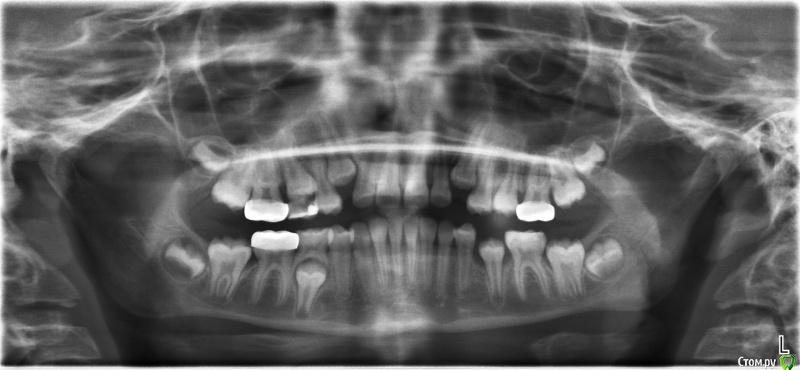

Винкс Опубликовано 22 декабря, 2017 Поделиться Опубликовано 22 декабря, 2017 Ребенок 11 лет, надо ли ждать прорезывания клыков или уже бежать к доктору. Ссылка на комментарий